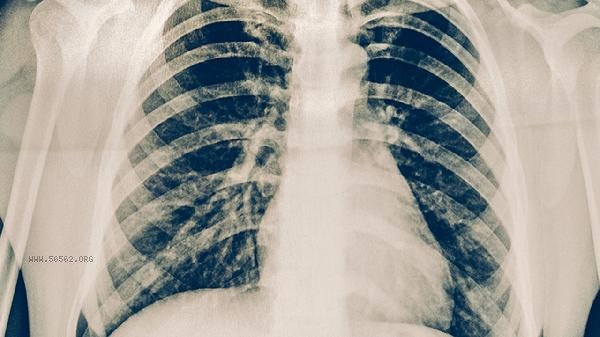

Physical examination chest X-ray can detect some lung cancer, but the detection rate is low and it is easy to miss early lung cancer. Lung cancer screening mainly relies on more accurate examination methods such as low-dose spiral CT.

Chest X-ray can observe lung structure through X-ray imaging and has a certain detection ability for central lung cancer with larger diameter or advanced lung cancer with obvious atelectasis and pleural effusion. This type of tumor usually exceeds 3 centimeters and may be accompanied by typical signs such as mediastinal lymph node enlargement or rib destruction. However, the resolution of chest X-ray is limited, making it difficult to identify pulmonary nodules smaller than 1 centimeter, ground glass lesions, or lesions located in concealed areas such as the apex of the lung and the spine, which are often manifestations of early lung cancer. There is still a limitation of overlapping tissues before and after chest X-ray, which may lead to a missed diagnosis rate of over 20%. Low dose spiral CT can detect tiny nodules larger than 2 millimeters, and its detection rate for early lung cancer is 4-10 times higher than chest X-ray. International lung cancer screening studies have confirmed that high-risk individuals who receive low-dose CT scans annually can reduce lung cancer mortality by 20%. For populations with long-term smoking, a family history of lung cancer, or occupational exposure, low-dose CT is recommended as a routine screening method. Chest X-ray is more suitable as a preliminary examination method for emergencies such as pulmonary infections and pneumothorax. If abnormal shadows are found on chest X-ray, further diagnosis through enhanced CT, PET-CT, or pathological biopsy is required. People over 40 years old should pay attention to lung cancer screening and improve early diagnosis rates by combining tumor marker testing. In daily life, it is necessary to avoid smoking and exposure to secondhand smoke, pay attention to kitchen fume protection, and seek medical attention promptly when symptoms such as persistent coughing and bloody sputum occur.